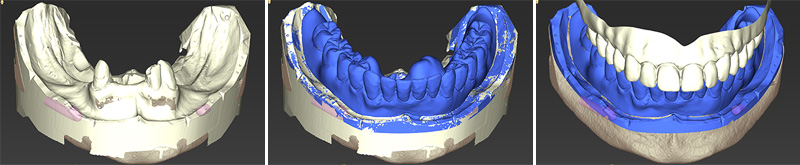

Fig. 12, 13 et 14 : le rendu surfacique de la numérisation au format STL de l’empreinte secondaire, la prothèse diagnostique et l’antagoniste.

Sur les données DICOM, sont empilés le rendu surfacique de la numérisation au format STL de l’empreinte secondaire, la prothèse diagnostique et l’antagoniste. Ce dernier est la numérisation du montage directeur polymérisé en prothèse complète conventionnelle.

Fig. 39 et 40 : les différentes vues du second cas.

Nous retrouvons maintenant comme précédemment les différentes vues du cas n°2 : l’os (en vert) et les dents segmentées (en rouge) et le rendu surfacique de l’arcade à l’état initial (en beige). À noter que bien que l’empreinte soit en couleur au format ply (fig. 38), les prothésistes convertissent le fichier en monochrome.

Fig. 41 et 42 : un masque gingival (en rose), est créé par soustraction des dents sur le rendu surfacique puis les dents segmentées (en rouge) sont virtuellement extraites et remplacées par un wax-up numérique en accord avec le maxillaire déjà traité.